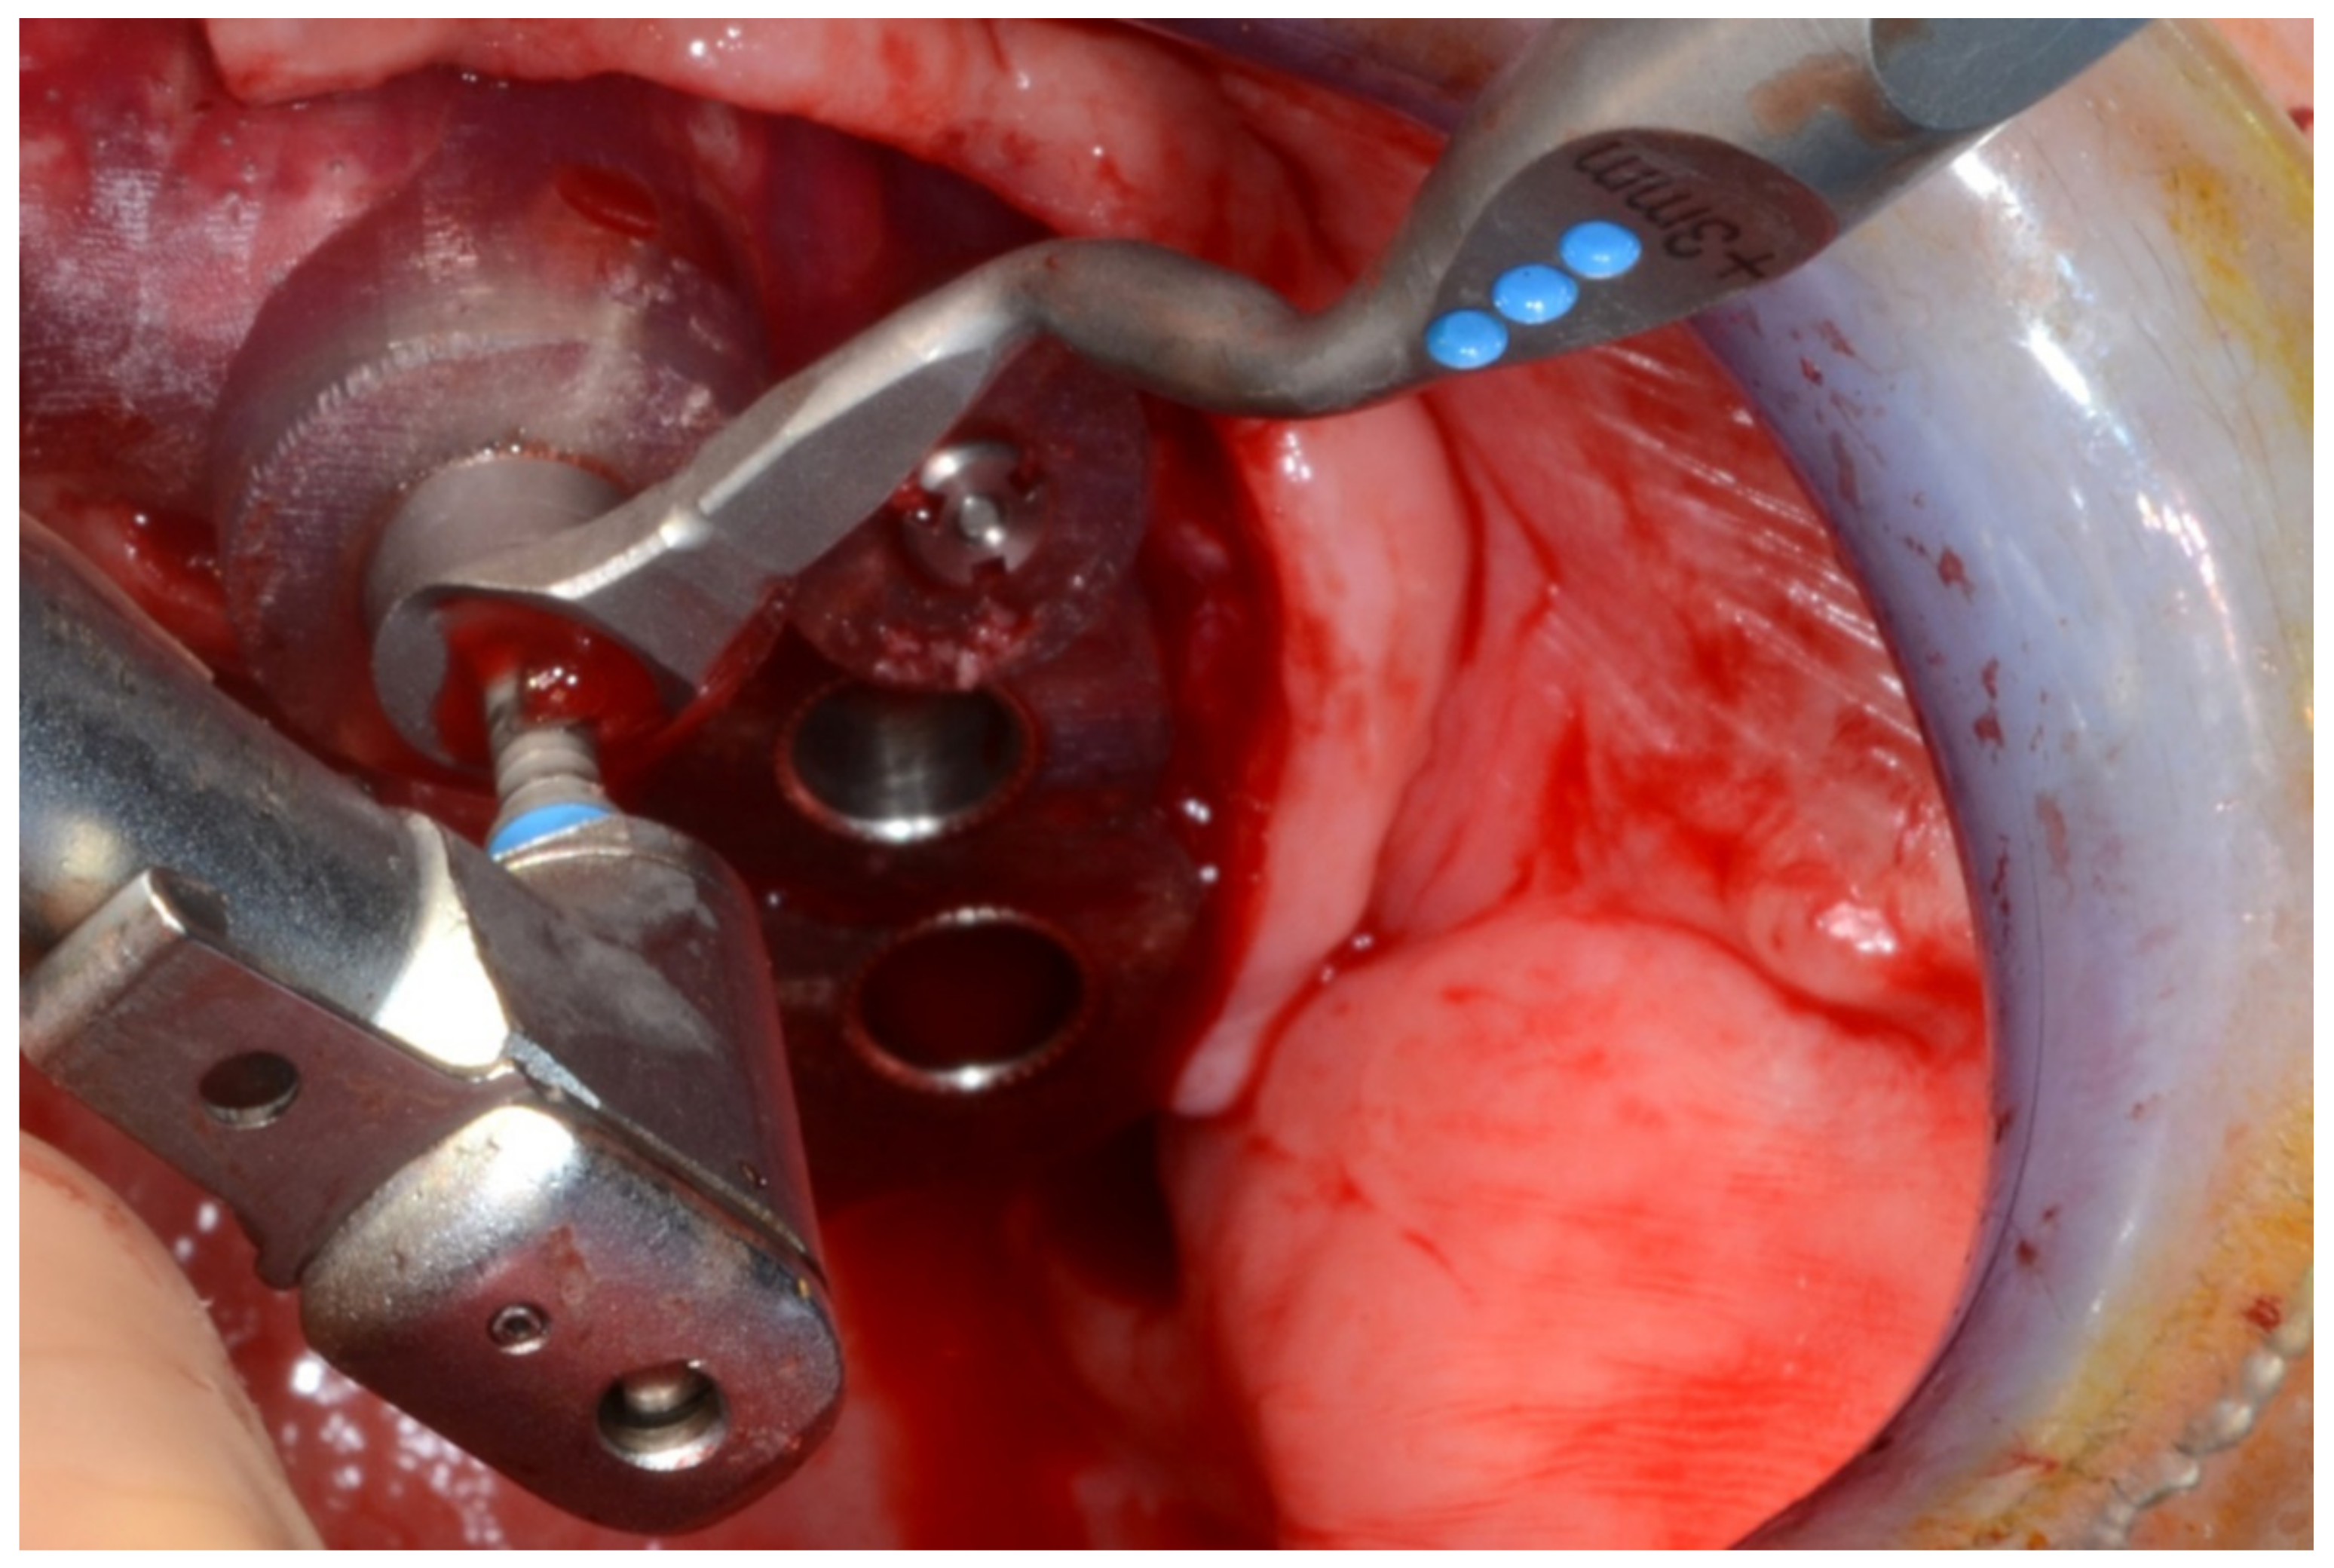

6.2.4. Intra-Operative Documentation:

In March 2013, twelve guided dental implants were placed at sites # 12, # 13, # 15, # 22, # 23, # 25, # 33, # 34, # 36, # 43, # 44, and # 46 (Figure 22, Figure 23, Figure 24, Figure 25 and Figure 26)

Figure 23.

Mandibular surgical drilling guides temporarily supported and fixed with mini-screws.

Figure 24.

Implant bed preparation using guided drills inserted into specific ad hoc drill handles.